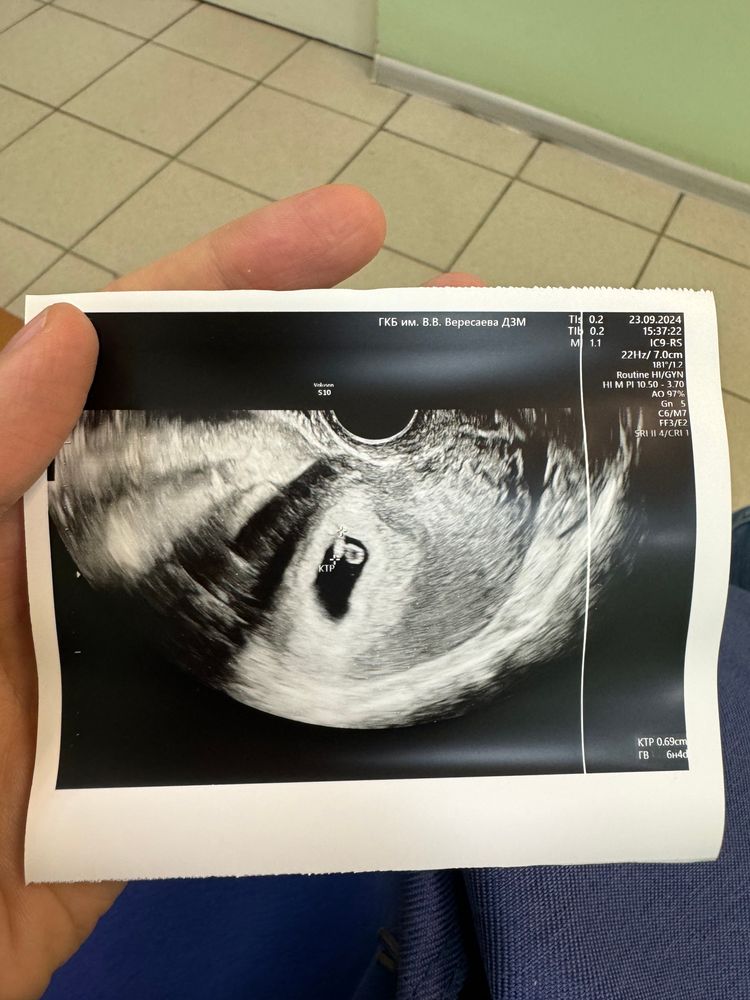

У меня тоже первый день месячных 11 августа. Фото узи от 23 сентября. Если поможет сориентироваться..

Девочки, подскажите, врач говорит, что задержка развития беременности, подозрение на неразвивающуюся, живот не болит, выделений нет, на первом узи 26.09 обнаружили плодное яйцо диаметром 18мм, ктр 5мм, на втором узи 03.10 внутренний диаметр плодного яйца 30мм, ктр 7, у меня паника, последний день менструации 11 августа, 26.09 хгч был 6000, 28.09 хгч был 10000, 04.10 хгч 30155

Анастасия, по первому УЗИ у вас все отлично,но вот второе не радует,у меня первое узи почти анологично было,пя 19,ктр 5,4 и ЧСС 146 уд/мин,повторно через 11 дней пя 28, ктр 18 и ЧСС 180 уд/мин,за 11 дней эмбрион с 5 мм вырос до 18 мм

Повторите узи в другой клинике, но на фото по узи малыш почти не вырос, тут только надеяться на чудо